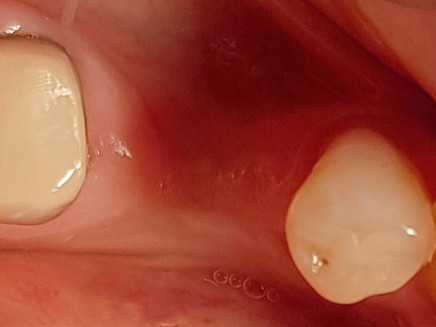

Имплантация

Проведена стандартная процедура имплантации в 2 этапа: установка импланта и формирование десны для создания ровного десневого контура.

После этого пациент был направлен к стоматологу-ортопеду для проведения протезирования на импланте.

Доктор: Биктимиров Андрей Евгеньевич